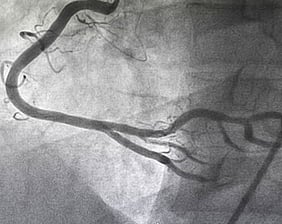

Angiogram

(also coronary angiogram, cardiac catheterisation)

This is a special x ray test to actually take pictures of the arteries of the heart. It is a very safe test and is performed under local anaesthetic. A tiny tube is passed to the heart via an artery in either the leg or wrist and moving x-ray pictures recorded as a special dye is injected into the arteries. This gives us a road map of the arteries and shows up any blockages or narrowings. During this test the valves, pumping function and oxygen levels in the heart can also be assessed.

Remember this is an investigation not a treatment which is why it is much cheaper than angioplasty and stent insertion.